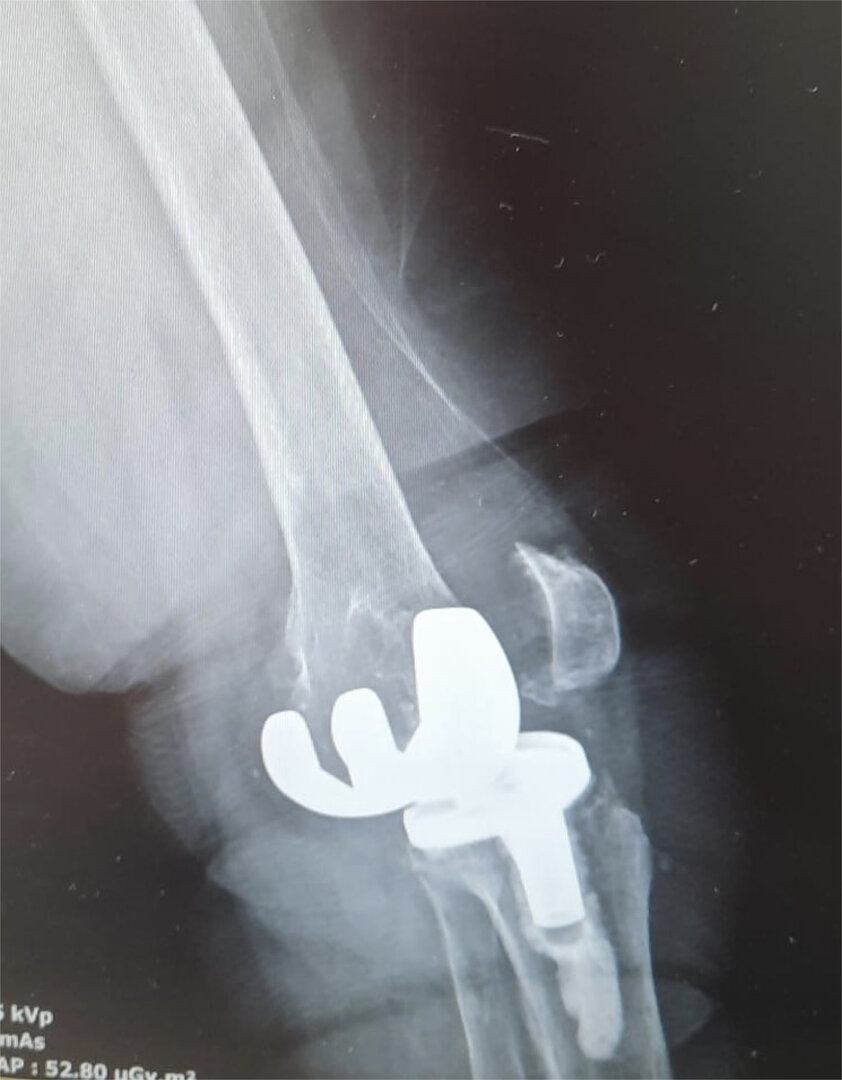

Aşınmış, hasar görmüş ya da eklem yüzeyleri tamamen bozulmuş diz ekleminin, yapay bir eklemle değiştirme işlemidir. Ameliyatta, ağrıya neden olan hasarlı kemik ve kıkırdak dokular çıkarılarak; yerine metal ve özel plastikten yapılmış, uzun ömürlü bir protez yerleştirilir. Bu sayede diz, tekrar ağrısız ve stabil bir şekilde çalışır hale gelir.

Eklem yüzeyleri özel kılavuzlar yardımı ile temizlendikten sonra metal protez eklem yüzeylerine bir kemik çimentosu ile adapte diyoruz. Bu iki metal yüzeyin sürtünmesini azaltmak için polietilenden yapılmış özel bir plastik tabakayı sisteme dahil ediyoruz.